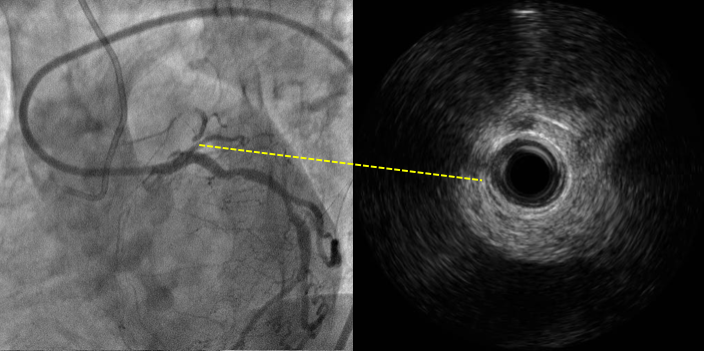

结合IVUS图像确认穿刺点及穿刺方向

MC+ pilot 150, crossed

Final result